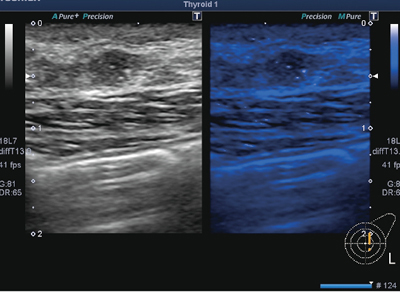

●微細な構造物をより見やすく“MicroPure”(図2)

微細な構造物を抽出し,その視認性を向上させるモードです。“Differential THI”など東芝独自の高画質化技術による高空間分解能の画像から,乳腺に特化したフィルタで抽出した微小石灰化などの構造物を,blue layerをバックに浮き上がらせて見やすくするアプリケーションです。

図2 MicroPure